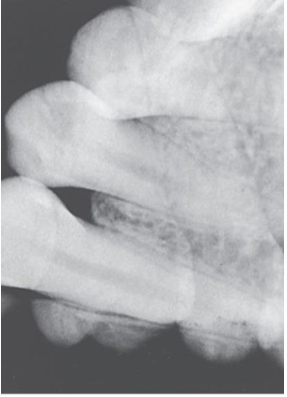

What is the problem with this Phalangioma X-ray?

May occur with digital sensors or film,Patient’s finger was positioned in front of the receptor during finger-holding method

How would you resolve this Phalangioma X-ray?

Never allow the patient to hold a receptor during exposure